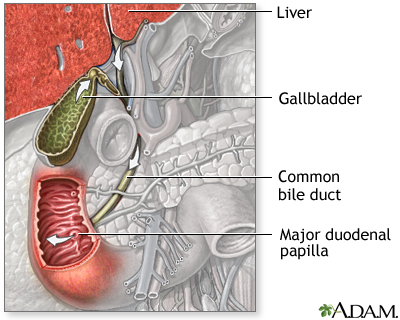

Choledocholithiasis means there is at least one gallstone in the common bile duct. The stone may be made up of bile pigments or calcium and cholesterol salts and are called common bile duct stones.

About 1 in 7 people with gallstones will develop stones in the common bile duct. This is the small tube that carries bile from the gallbladder to the intestine.

- ERCP and a procedure called a sphincterotomy, which makes a surgical cut into the muscle in the common bile duct to allow stones to pass or be removed